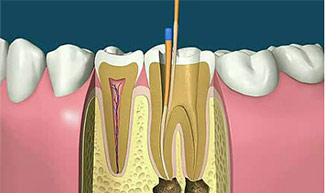

- 蛀牙做了根管治疗后,有些患者苦不堪言,原因是牙齿咬合根部还是会痛,一般牙医抽完牙神经,牙齿失去了活力,为什么仍然还有痛的感觉?究竟牙齿出现什么情况,做根管治疗前你必须知道这些。

根管治疗是国际公认的治疗牙髓根尖周病保存牙齿的最好方法。完善的根管治疗较其它牙髓治疗难度大,治疗更彻底,但是浪费时间,费用也高。随着科技发展,根管治疗所用的材料和设备也越来越先进,比如根管长度测量仪,根管马达,镍钛锉,热牙胶充填仪,牙科显微镜,数字牙片机等的使用大大提高了疑难根管治疗的成功率。

1、根管治疗不完善:根管治疗过程中,根管清理不彻底、充填不完善,导致根尖周病变范围无减小,甚至扩大,应及时再次进行根管治疗,以消除病变范围,促进根尖周病变愈合;

2、根尖清理不彻底:根尖周围病原刺激物及细菌清理不彻底导致,即使根管严密三维充填,X线下根尖周病变范围明显缩小或愈合,仍可引起疼痛或不适症状,可将牙齿调低,使其承载咬合力减弱或者进行显微根尖手术治疗。